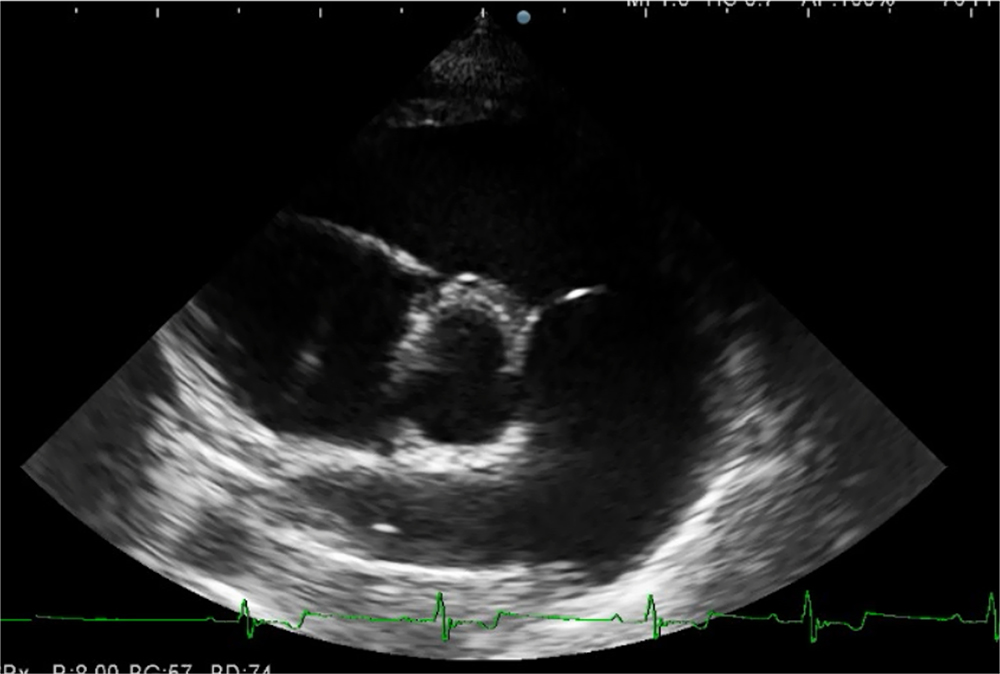

心エコー検査

心エコー検査では、超音波を用いて心臓の形態や動きをリアルタイムで観察できます。

心エコー検査は、

- 心臓の大きさ

- 心臓の壁の厚さ

- 弁の状態

- 血流の様子

などを詳細に評価できます。

非侵襲的で痛みを伴わず、短時間で行えるため、循環器疾患の診断に欠かせない検査です。

猫の肥大型心筋症

猫の肥大型心筋症は心臓の筋肉が厚くなることで心臓の動きが障害され、全身に十分な血液を送り出せなくなる病気です。 肥大型心筋症は特定の猫種において発生しやすいことが知られています。特にメインクーンやラグドールなどの純血種に多く、遺伝的要因が関与していると考えられています。 猫の肥大型心筋症は、初期段階ではほとんど症状が現れないため、飼い主様が気づくことは難しいです。 しかし、病気が進行すると、呼吸困難や突然倒れてしまうなどの重篤な症状が現れることがあります。 肥大型心筋症は早期発見が難しいため、定期的な健康診断がおすすめですね。 健康診断では血液検査だけではなく、レントゲン検査や心エコー検査といった画像検査も行うことで病気の早期発見につながります。 当院ではこれらの検査を通じて猫の心臓の状態を正確に把握し、適切な治療方針を立てることができます。